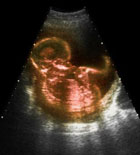

孕期B超

B超是产前检查的一个项目,主要是为了监测胎儿是否存在严重畸形。如体表畸形、内脏畸形等,但并不是每一个都能发现;怀孕早期B超以测量妊娠囊、顶臀长,可以以此确定预产期,和排除异位妊娠;妊娠中晚期测量双顶径、腹围及股骨长度,可了解胎儿的生长发育情况;确定胎儿的位置,区分是头位还是臀位,以及确定胎盘的位置及成熟度;确定胎儿个数,了解羊水量以及测量S/D值,观察胎心是否正常。